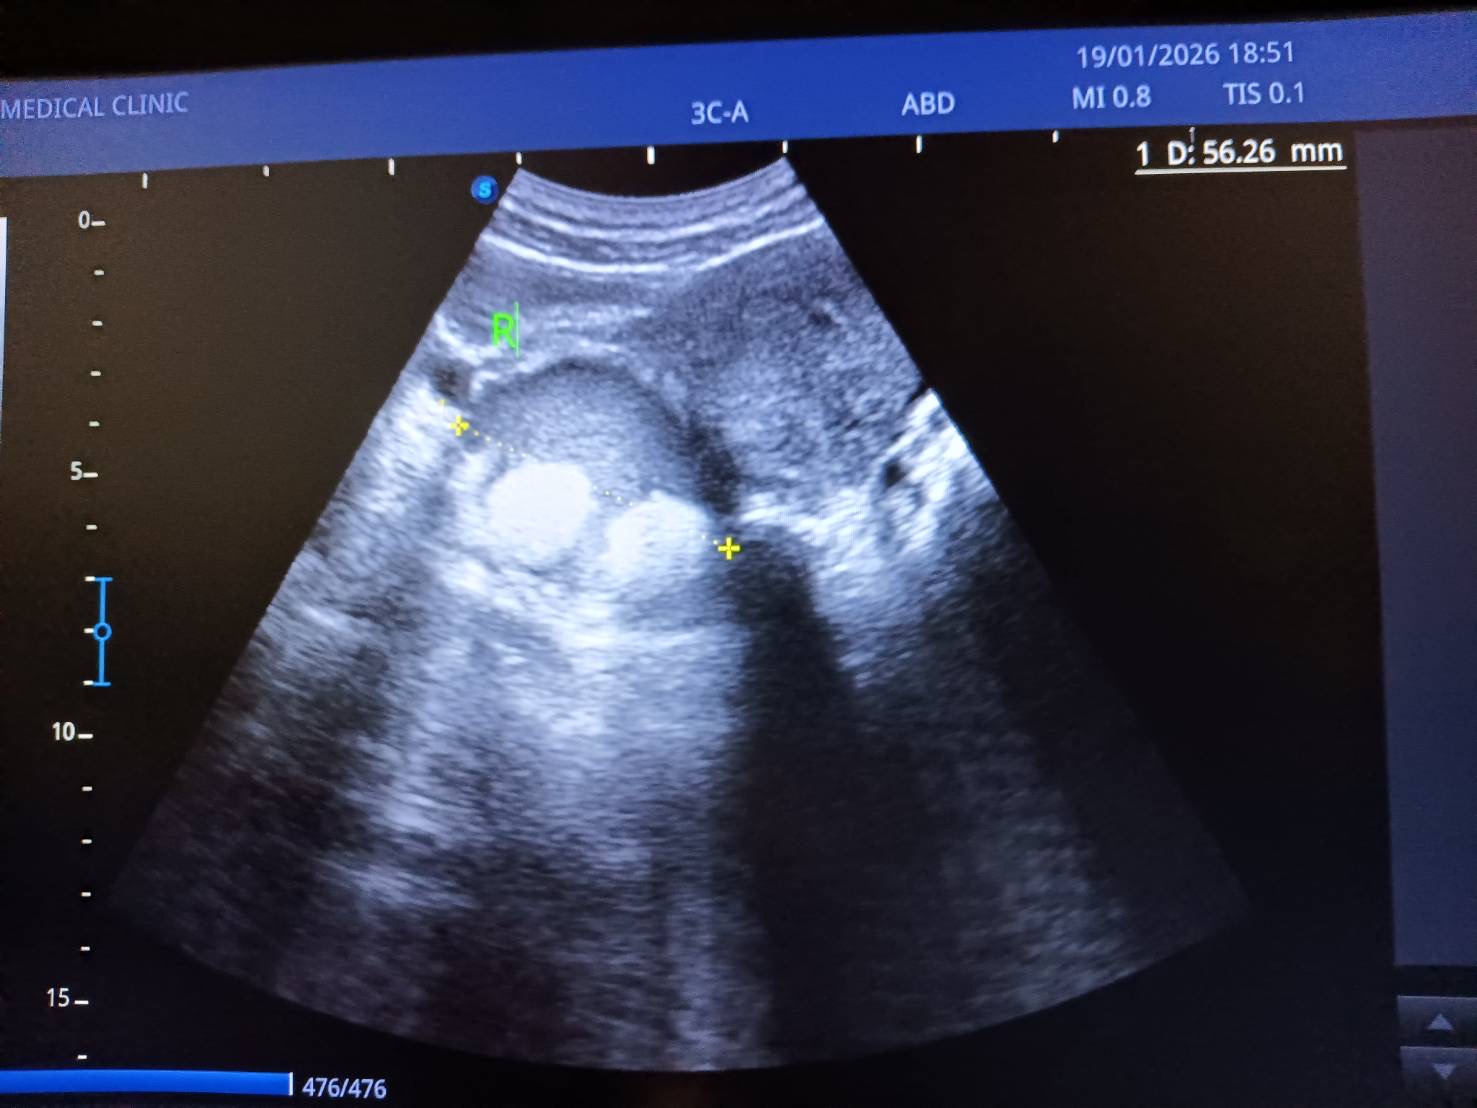

ใครเคยตรวจเจอซีสในรังไข่

อันนี้กระทู้แรกในชีวิตเรา เราอยากรู้ว่าภาพนี้คือ ซีสหรอ แล้วขาวๆ 2 วงกลมคืออะไร วงใหญ่ดำคือซีสใช่หรือเปล่า???